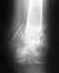

Постоянно присутствующая ноющая (не острая) боль в стопе, не проходит более 2-х месяцев. Больно вставать на ногу после того, как продолжительное время проводишь в сидячем положении (вплть до временной хромоты). Несколько лет назад был достаточно сильный вывых, но до настоящего времени никаких его последствий не ощущалось. Подскажите, пожалуйста, возможно ли записаться на консультацию к специалистам УНИИТО и в каком порядке это делается (к сожалению, телефоны, указанные на сайте, не отвечают). Спасибо!